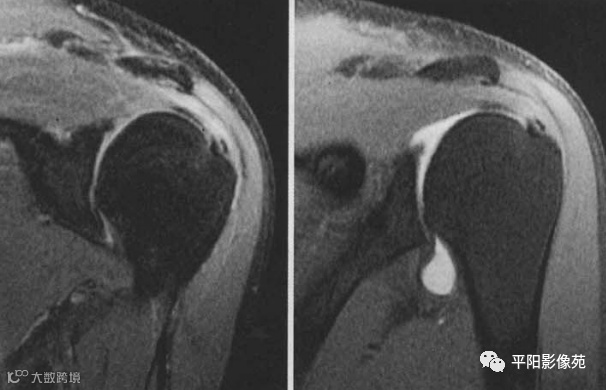

肌腱部分撕裂,示例

3、冈上肌肌腱内部分撕裂,造影剂未进入肌腱

4、小圆肌关节面部分撕裂

5、肩胛下肌关节面部分撕裂